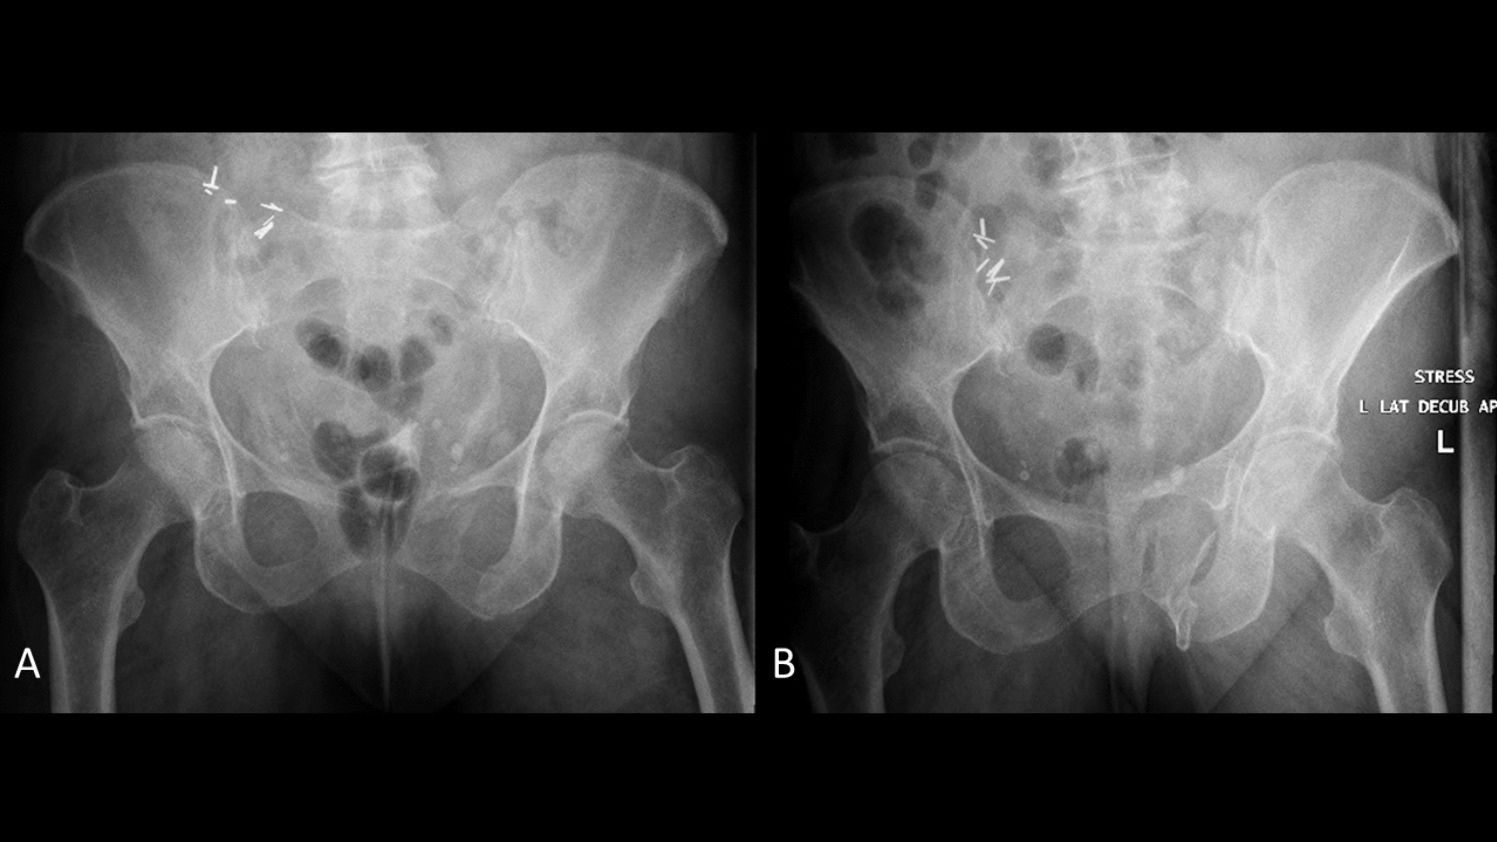

The use and usefulness of stress imaging for guiding treatment decisions for minimally displaced LC injuries with minimally displaced posterior ring injuries are also controversial [1]. Multiple studies have demonstrated that these injuries have low rates of fracture displacement and high rates of union, however when these do occur, they are difficult to treat [11, 12, 4648]. As a result, examination under anesthetic (EUA) was described as a method to identify fractures with occult pelvic ring instability that may be at higher risk for subsequent fracture displacement and/or poor outcomes. Kanakaris and colleagues described the use of an internal rotation stress examine under anesthesia in 40 patients with LC1 pelvis fractures. 23 patients (58%) demonstrated > 2 cm of displacement on fluoroscopic manipulation and were treated with sacroiliac screws in combination with retropubic screws, external fixator or anterior pelvic plating. Tsounidis et al. expanded this series, observing that patients who demonstrated > 2cm displaced and were managed surgically experienced less pain at 72 h, shorter hospital stay, shorter time to pain-free mobilization, and decreased opioid use [49]. Sagi and colleagues independently and concurrently described a more thorough EUA of the pelvis including compression over the trochanters to detect instability to internal rotation forces and a push–pull exam of the lower extremities to detect vertical instability on AP, inlet, and outlet images (Fig. 1) [31]. This group reported that 35% (7/20) of minimally displaced LC1 fractures displaced > 1 cm on fluoroscopy with EUA and were treated with operative fixation.

Fig. 1

(A) Non-stress and (B) stress fluoroscopic images from an examination under anesthesia of a 77-year-old woman with a minimally-displaced LC1 fragility fracture of the pelvis demonstrating gross occult instability

The lateral stress radiograph, an anteroposterior (AP) pelvis radiograph taken in the lateral decubitus position, is an alternative to EUA that avoids many of the above limitations (Fig. 2) [18]. The lateral stress radiograph requires no anesthetic or sedation, can be done in the emergency department by radiologist technicians without physician supervision, and applies a relative standardized force using gravity and the patient’s body weight. Fractures can be objectively measured on the radiograph using the electronic imaging system and compared to standard supine AP pelvis radiographs to determine displacement. In a series of 131 consecutive patients receiving lateral stress radiographs, 62.5% (n = 80) of patients had occult instability, defined as ≥ 1 cm of dynamic displacement [32]. The median age of the cohort was 57 years, 60% were female, and 52% had low-energy mechanisms. Patients with occult instability, compared to those without, were older (63 vs 48 years; p = 0.009), more likely to have parasymphyseal rami fractures (74% vs 48%; p < 0.0001), and rami comminution (96% vs 38%; p < 0.0001). Occult instability had no association with high-energy injury mechanisms, sacral fracture completeness, or sacral fracture comminution. Limitations of the lateral stress radiograph include pain, with some patients being unable to tolerate the lateral position, the potential for malrotated radiographs that can make interpretation difficult, and the difficulty of obtaining in polytraumatized patients with long bone or spine fractures [51].

Fig. 2

(A) AP pelvis radiograph and (B) lateral stress radiograph of the same patient from Fig. 1 redemonstrating the gross occult instability